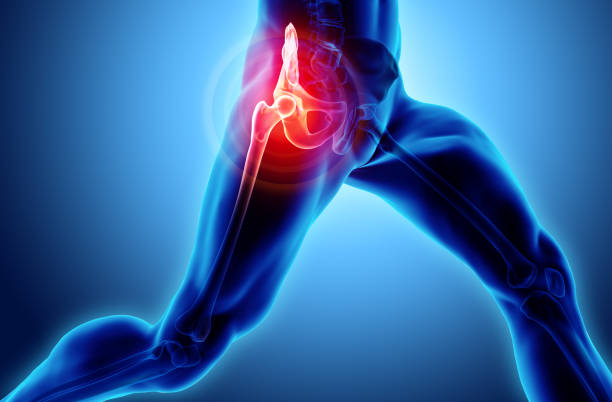

고관절 통증 증상 치료와 관리

고관절 통증을 관리하고 치료하기 위해서는 다양한 요인을 고려해야 합니다. 통증을 완화하고 원인을 해결하기 위해 개별 환자에게 맞춤형 치료 계획이 필요합니다. 이때, 관절과 근육의 조화로운 기능을 회복시키기 위한 재활운동이 중요합니다.

고관절 통증 증상 예방

고관절 통증을 피하기 위해서는 예방이 중요합니다. 특히, 허리와 고관절을 지지하는 근육을 강화하는 운동은 큰 도움이 됩니다. 이러한 운동은 40대부터 시작하여 허리와 관절의 건강을 유지하는 데 도움을 줄 수 있습니다.